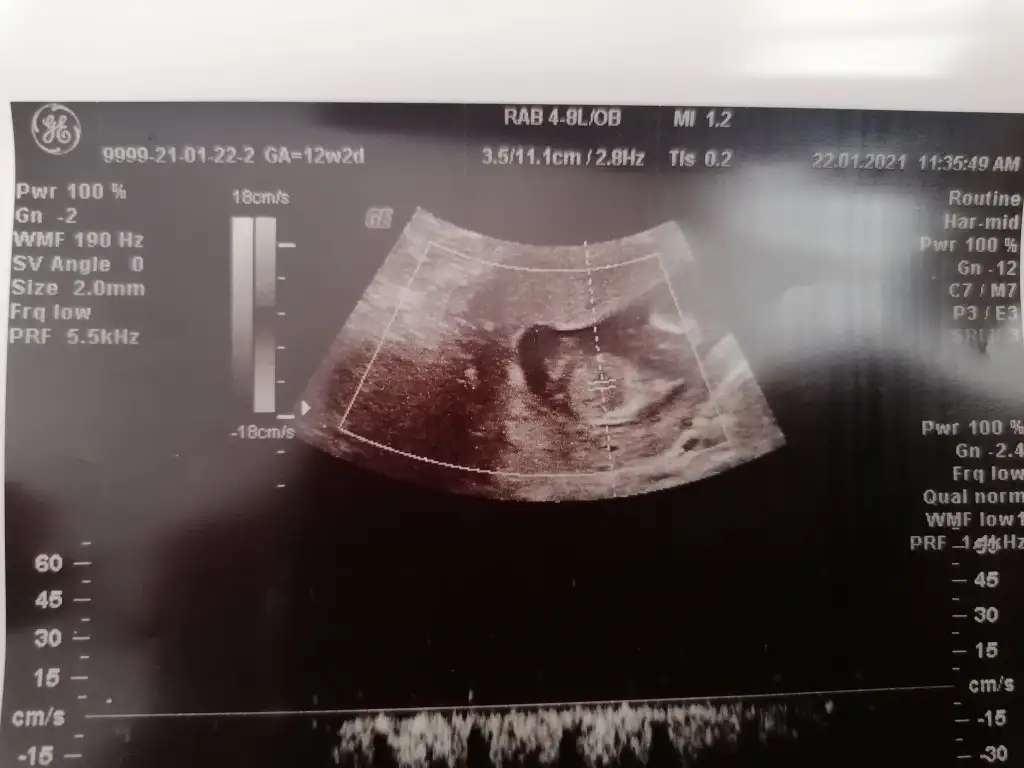

Merhaba Ikra meyra Ikra meyra bugun tekrar kontrol gittim atıyorum 12+2 🤗

• IMG_20210122_124005.webp

IMG_20210122_124005.webp

26,3 KB · Görüntüleme: 84